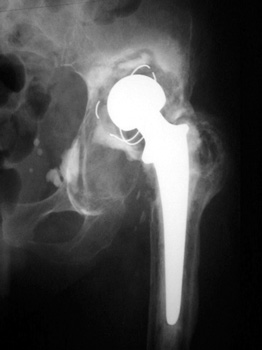

OSTEOLYSIS—Gruen zones 2 and 3, with markedly thinned femoral cortex, placing patient at risk for pathologic fracture

OSTEOLYSIS—ABOUT ACETABULAR COMPONENT GRUEN ZONE II, WITH PATHOLOGIC FRACTURE